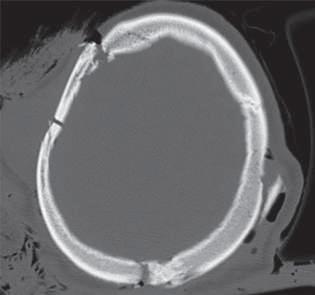

Lesões Ósseas

Palavras-chave: fraturas ósseas.

Keywords: bone fractures.

Introdução

O esqueleto do corpo humano é constituído por 206 ossos que são responsáveis pelas mais diversas funções, nomea damente: proteção dos órgãos internos, suporte mecânico, regulação da homeostasia mineral, funções hematopoiéti cas. Ao contrário dos outros tecidos no corpo humano que após lesão regeneram com tecido cicatricial, o tecido ósseo regenera com osso novo, indistinguível do osso original.

Devido à sua elevada área de exposição, o esqueleto apre senta, frequentemente, sinais de traumatismos, advindo daí a sua importância numa perspectiva médico-legal, quer em termos de patologia, quer de clínica forense. Após uma le são óssea, há a formação de um hematoma e uma resposta inflamatória que vai induzir a formação de osso novo por osteoblastos locais. Há a constituição de uma matriz co lagenosa e a diferenciação de células mesenquimatosas, com a formação de cartilagem. Os condrócitos proliferam, hipertrofiam e segregam fatores que vão induzir a ossifi cação da cartilagem, com a conversão de cartilagem em osso novo – ossificação endocondral. Este osso é remode lado pela ação combinada de osteoblastos e osteoclastos, dando origem a osso maduro de acordo com as linhas de stress/tensão (Clohisy et al., 2009). Dependendo do timing da lesão óssea, assim, poderemos ter lesões ante mortem, peri mortem e post mortem.

A presença de um calo ósseo, denotando assim um osso que teve tempo para maturar, aponta para uma lesão ante mortem. Já uma lesão que não apresenta sinais de conso lidação pode ter tido origem peri mortem ou post mortem A constituição do osso é alterada após a morte, com perda de água e da sua elasticidade, tornando assim o osso mais quebradiço, o que vai influenciar as características das lesões ósseas post mortem

Nas lesões peri mortem, encontra-se uma coloração mais uniforme e a presença de fraturas incompletas, em espiral e de tensão-compressão, frequentemente mais oblíquas. Nas lesões post mortem, em que o osso se encontra mais seco por desidratação, a coloração pode ser mais heterogénea

(por exposição ao meio envolvente), as superfícies de fratu ra vão apresentar-se mais regulares, com bordos retos, e as fraturas serão mais longitudinais e transversais irregulares (Cunha & Pinheiro, 2005/2006).

A forma e a aparência das lesões ósseas podem refletir não só a direção, a área, a velocidade, a massa e a forma do objeto produtor da lesão, mas também as próprias ca racterísticas inatas do tecido ósseo, como o seu conteú do mineral, as características físicas do osso em questão ou eventuais alterações patológicas do mesmo (Cunha & Pinheiro, 2005/2006). Sendo uma combinação de matéria orgânica e inorgânica, o tecido ósseo é capaz de sofrer de formação elástica e plástica antes da falência. Mas uma vez iniciada a fratura, esta propagar-se-á através do osso até que a energia seja dissipada.

Existem três tipos principais de lesões: cortantes, contun dentes e perfurantes. Quando há uma combinação destas, podemos ter lesões mistas, como as perfuro-contundentes provocadas por projéteis de armas de fogo. Por regra, os diferentes tipos de lesões apresentam características típi cas dos instrumentos responsáveis pelas mesmas, apesar de o mesmo instrumento poder ser responsável por diferen tes tipos de lesões e a mesma lesão poder ser provocada por instrumentos diferentes.

36.1

Lesões cortantes e corto-contundentes

As lesões provocadas por instrumentos cortantes vão de pender das características da sua lâmina, o que pode per mitir identificar o instrumento responsável pelas mesmas. É possível a análise da impressão provocada no osso – dos entalhes ósseos e dos seus bordos, paredes e pavimen tos – e identificar padrões nas estrias que permitam dis tinguir o tipo de instrumento. A análise das estrias através da microscopia eletrónica permite identificar imperfeições específicas das lâminas, o que pode levar à identificação do instrumento específico responsável por uma determi nada lesão. A partir da análise das lesões, pode ser ainda

© PACTOR 473

36

possível identificar a direção do movimento e os padrões de corte (Bartelink et al., 2001; Ciallella et al., 2002; Saville et al., 2007; Symes, 1992; Symes et al., 2001).

Assim, podemos encontrar lesões produzidas por instru mentos de gume liso, serrilhado ou complexo, simples ou duplo. Quando além da ação do gume o instrumento apre senta um peso elevado, vamos ter lesões de características mistas (corto-contundentes), como acontece com lesões

provocadas por machados, espadas ou catanas (Figura 36.1), que atuam pela ação do peso e do gume cortante (Humphrey & Hutchinson, 2001; Lewis, 2008).

As lesões ósseas do tipo cortante ou corto-contundente ocorrem em grande número no contexto de acidentes de trabalho com trauma dos membros superiores, nomeada mente das mãos (Figura 36.2).

Fig. 36.1 Lesão por catana

Fig. 36.2 Lesão por serra